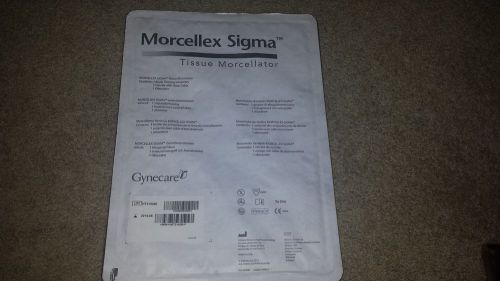

Morcellex Sigma Tissue Morcellator Gynecare